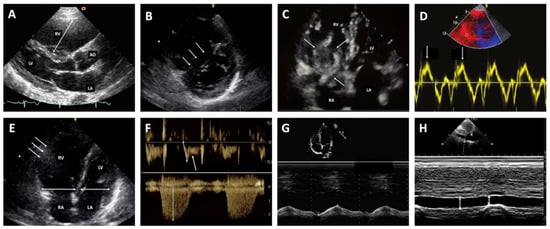

3.2. Diagnostic Strategy